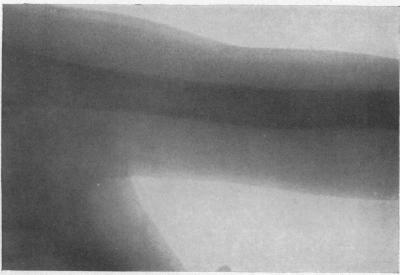

I. Benign Bone Cysts, Ostitis Fibrosa, Giant-Cell Sarcoma and Bone Aneurism of the Long Pipe Bones: A Clinical and Pathological Study with the Conclusion that Conservative Treatment is Justifiable.

Ann Surg. 1910 Aug;52(2):145-85. doi: 10.1097/00000658-191008000-00001.